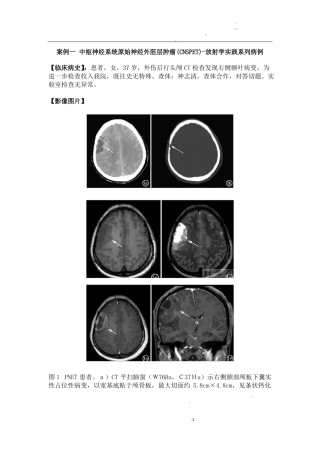

.......案例一 中枢神经系统原始神经外胚层肿瘤(CNSPET)-放射学实践系列病例【临床病史】:患者,女,37 岁,外伤后行头颅 CT 检查发现...